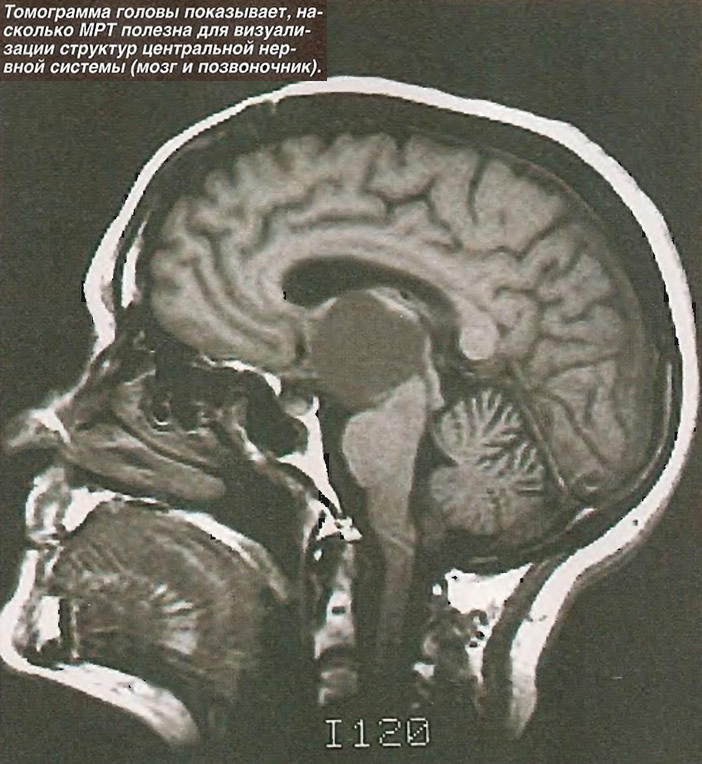

Внутричерепная гипотензия: КТ-исследования и их интерпретация